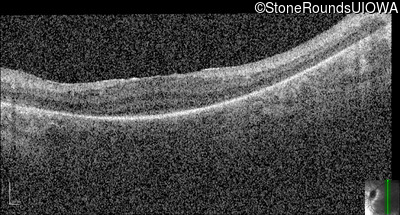

Optical Coherence Tomography - Right -

No Light Perception

Exemplar

Expanded OCT Stack

×

Optical Coherence Tomography - Left -